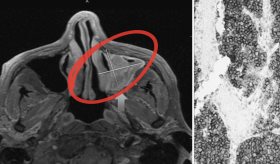

El linfoma extraganglionar de células NK/T es un subtipo raro de linfoma no Hodgkin que afecta principalmente a la cavidad nasal y otras áreas distintas a los ganglios linfáticos.